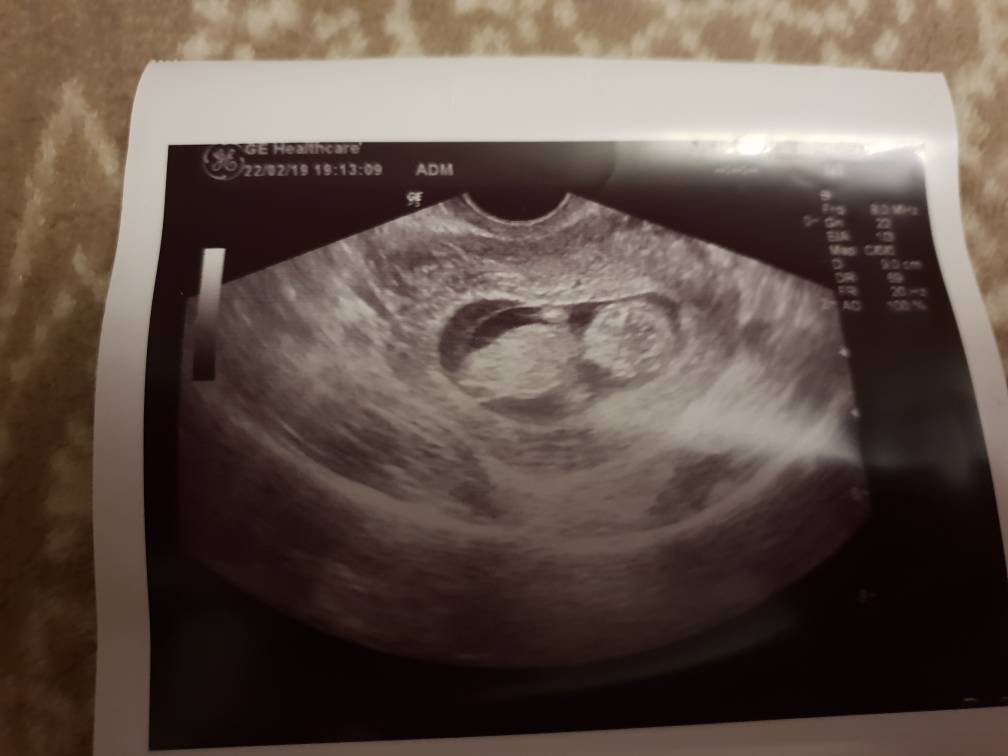

Już jestem po wizycie:) bejbika nie udało się zmierzyc, bo leżał nie tak jakby życzyła sobie tego Pani doktor. Poogladala tylko czy wszystko jest na swoim miejscu:) I powiedziała żebym 4 marca szła do jej kolegi po fachu, ponoć ma jeszcze lepszy sprzęt i będzie lepiej widać. A z dzisiejszej wizyty dowiedziałam się, że między nogami nic nie wisi [emoji23]

20190222_175659.jpeg